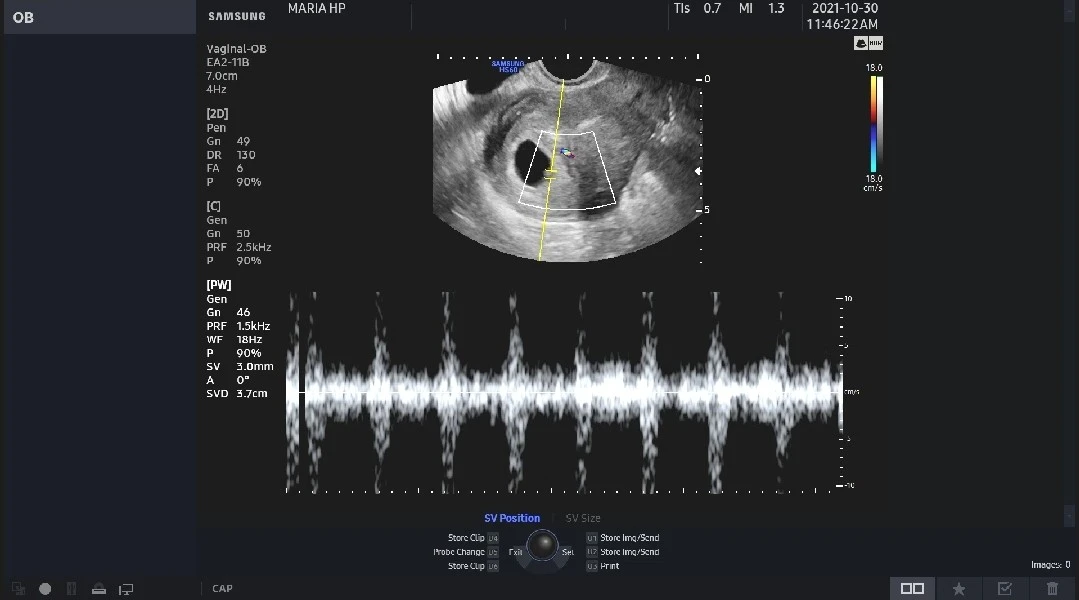

마지막 차례로 엄마의 이름이 불리었고 긴장된 걸음으로 진료실에 들어갔어. 1주일을 어떻게 보냈냐는 선생님의 인사에 아무렇지도 않았노라 답하고 초음파 검사 의자에 앉았어. 평소 늘 차분한 모습이셨던 의사 선생님이 고양된 목소리로 말씀하셨어. "보이네. 심장 뛰는 거 보이죠?" 엄마는 대체 어디를 봐야 하는지 도통 모르겠어서 고개를 갸웃하며 물었어. "네? 어디요? 어디가 심장이에요?" 의사 선생님이 마우스 커서를 가져가듯 화살표를 움직여 하얀 점을 가리키셨어. "여가 밝은 흰 점이 깜빡이잖아요. 가만있어봐. 들려줄게요." 쿵쾅쿵쾅쿵쾅~~~ "어머 선생님, 저 임신 6번 만에 이렇게 큰 심장 소리 처음 들어요" 엄마는 뺨을 타고 흐르는 뜨거운 눈물을 느낄 수 있었어.

활자로만 접하던 '벅찬 감동'이나 '환희의 눈물'과 같은 단어가 어떤 감정인지 엄마는 그제야 제대로 이해할 수 있었어. 여전히 작은 흰 점에 불과한 네가, 그보다 더 작은 흰 점인 너의 심장이 쿵쾅거리며 내게 신호를 보내고 있었어. 불안해하지 말라고, 걱정하지 말라고. 너의 그 강한 마음이 전해졌는지 엄마는 이전처럼 극도의 불안과 떨림을 느끼지 않았어. 매일매일 시간에 맞춰 의사 선생님이 처방해 주신 유산 방지 약을 먹고, 질정을 넣고, 주사를 맞으면서도 그토록 덤덤한 내 마음이 신기할 정도였어. 딱풀이가 쿵쾅거리는 심장 소리에 담아 보내 응원의 메시지 덕분이었겠지? 고맙고 사랑해 딱풀아~♡